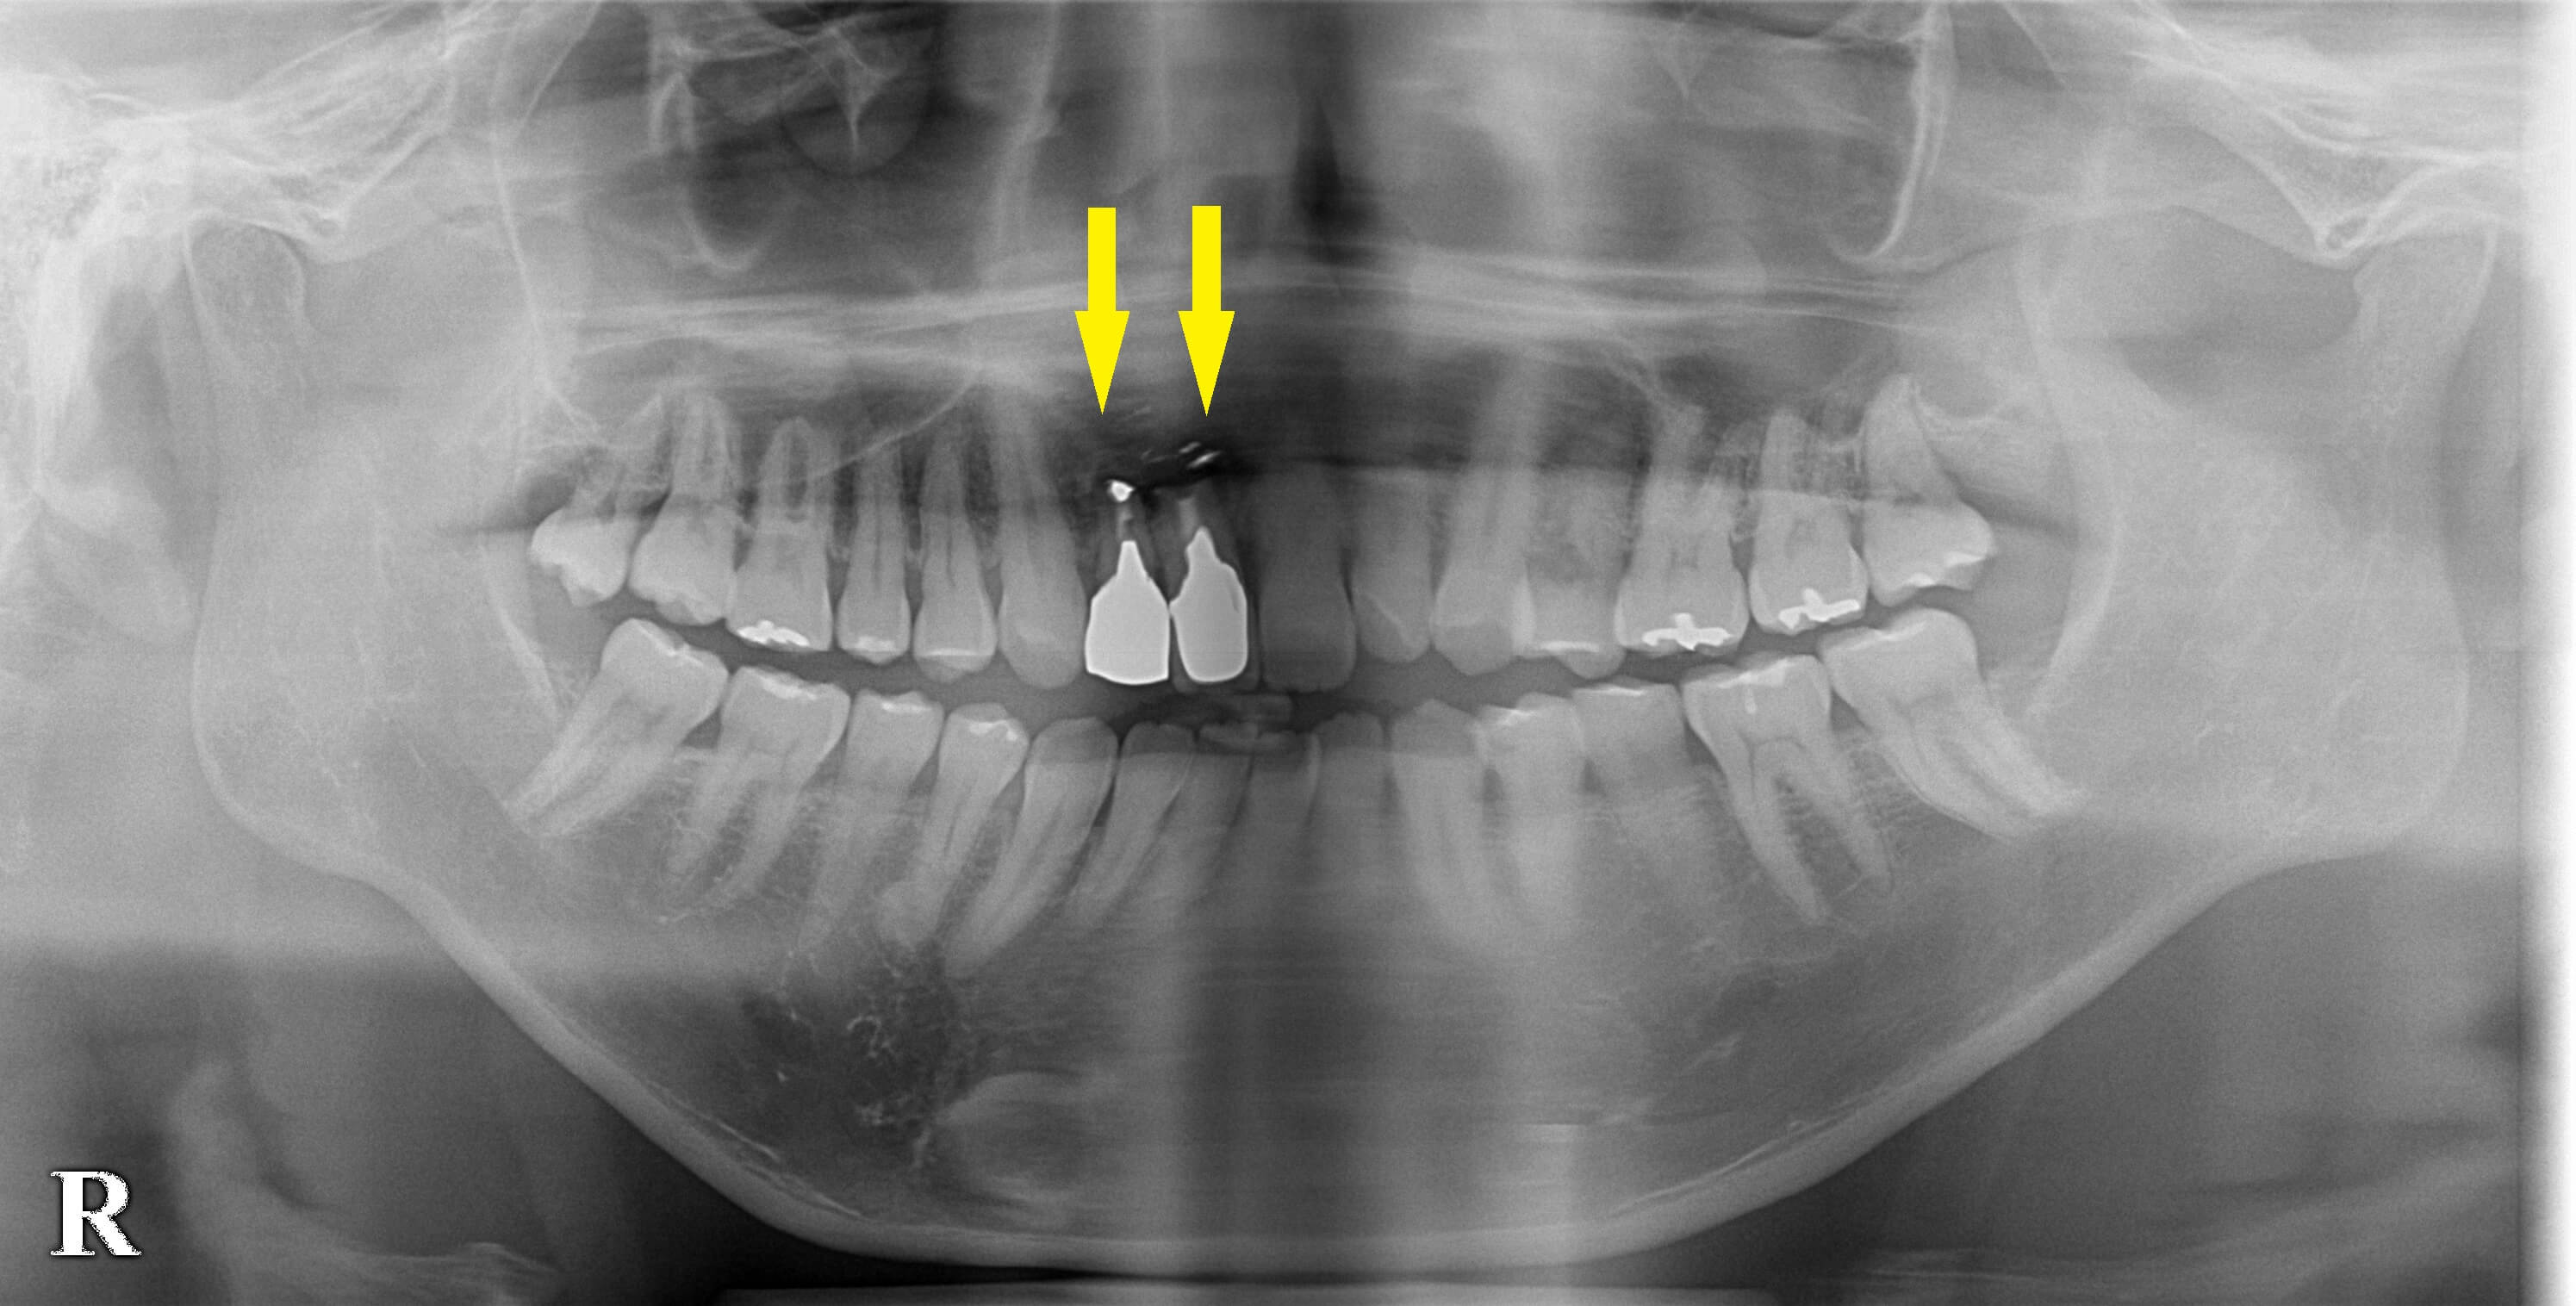

さらに歯根端切除術といって、歯根の先の感染した部位を削除して、外科的に切除する方法があるのですが、それを行っても、歯根の先から膿が出てきたり、腫れたりを繰り返していたそうです(下の写真上段)。

とうとう抜歯ということで、インプラント治療を希望されたのですが、CTを撮ってみると骨が薄くて、通常のインプラント埋入はできませんでした。